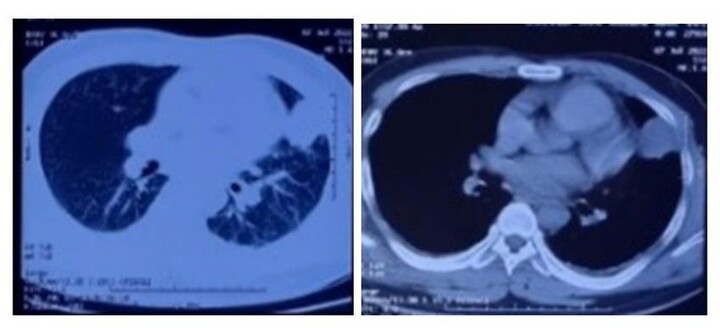

Kết quả cấy máu cho thấy người đàn ông bị nhiễm khuẩn máu do vi khuẩn Whitmore gây viêm phổi.